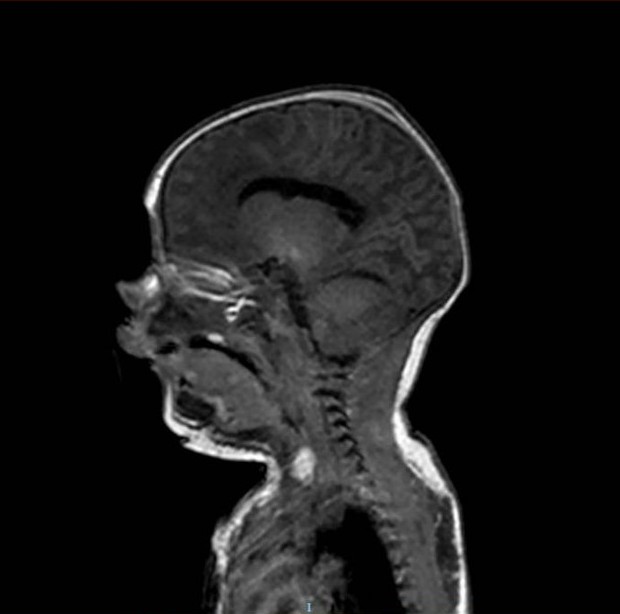

Se realiza tomografía computarizada (TC) craneal urgente al nacimiento (Figura 2).

Figura 2. TC craneal realizada al nacimiento donde no se aprecia hidrocefalia.